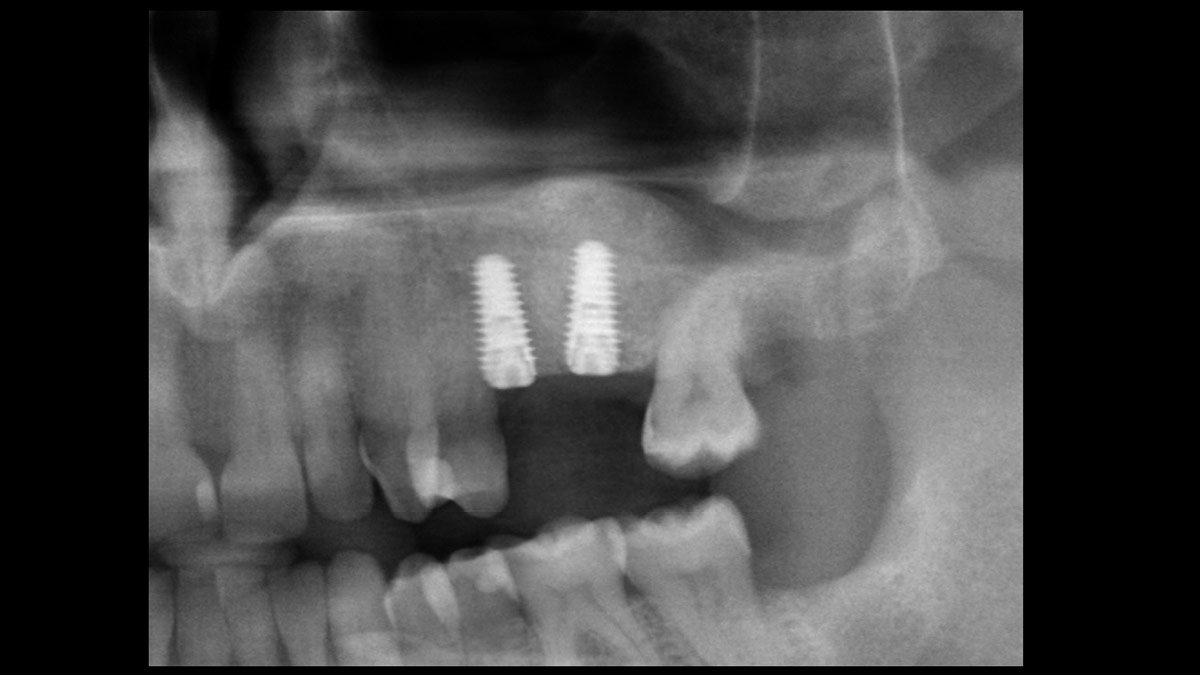

Delayed implant placement; sinus floor elevation by means of lateral approach and implant placement with GBR. Case report by Irfan Abas, M.Sc.

Immediate molars predictable? A case by @immediate_implantology